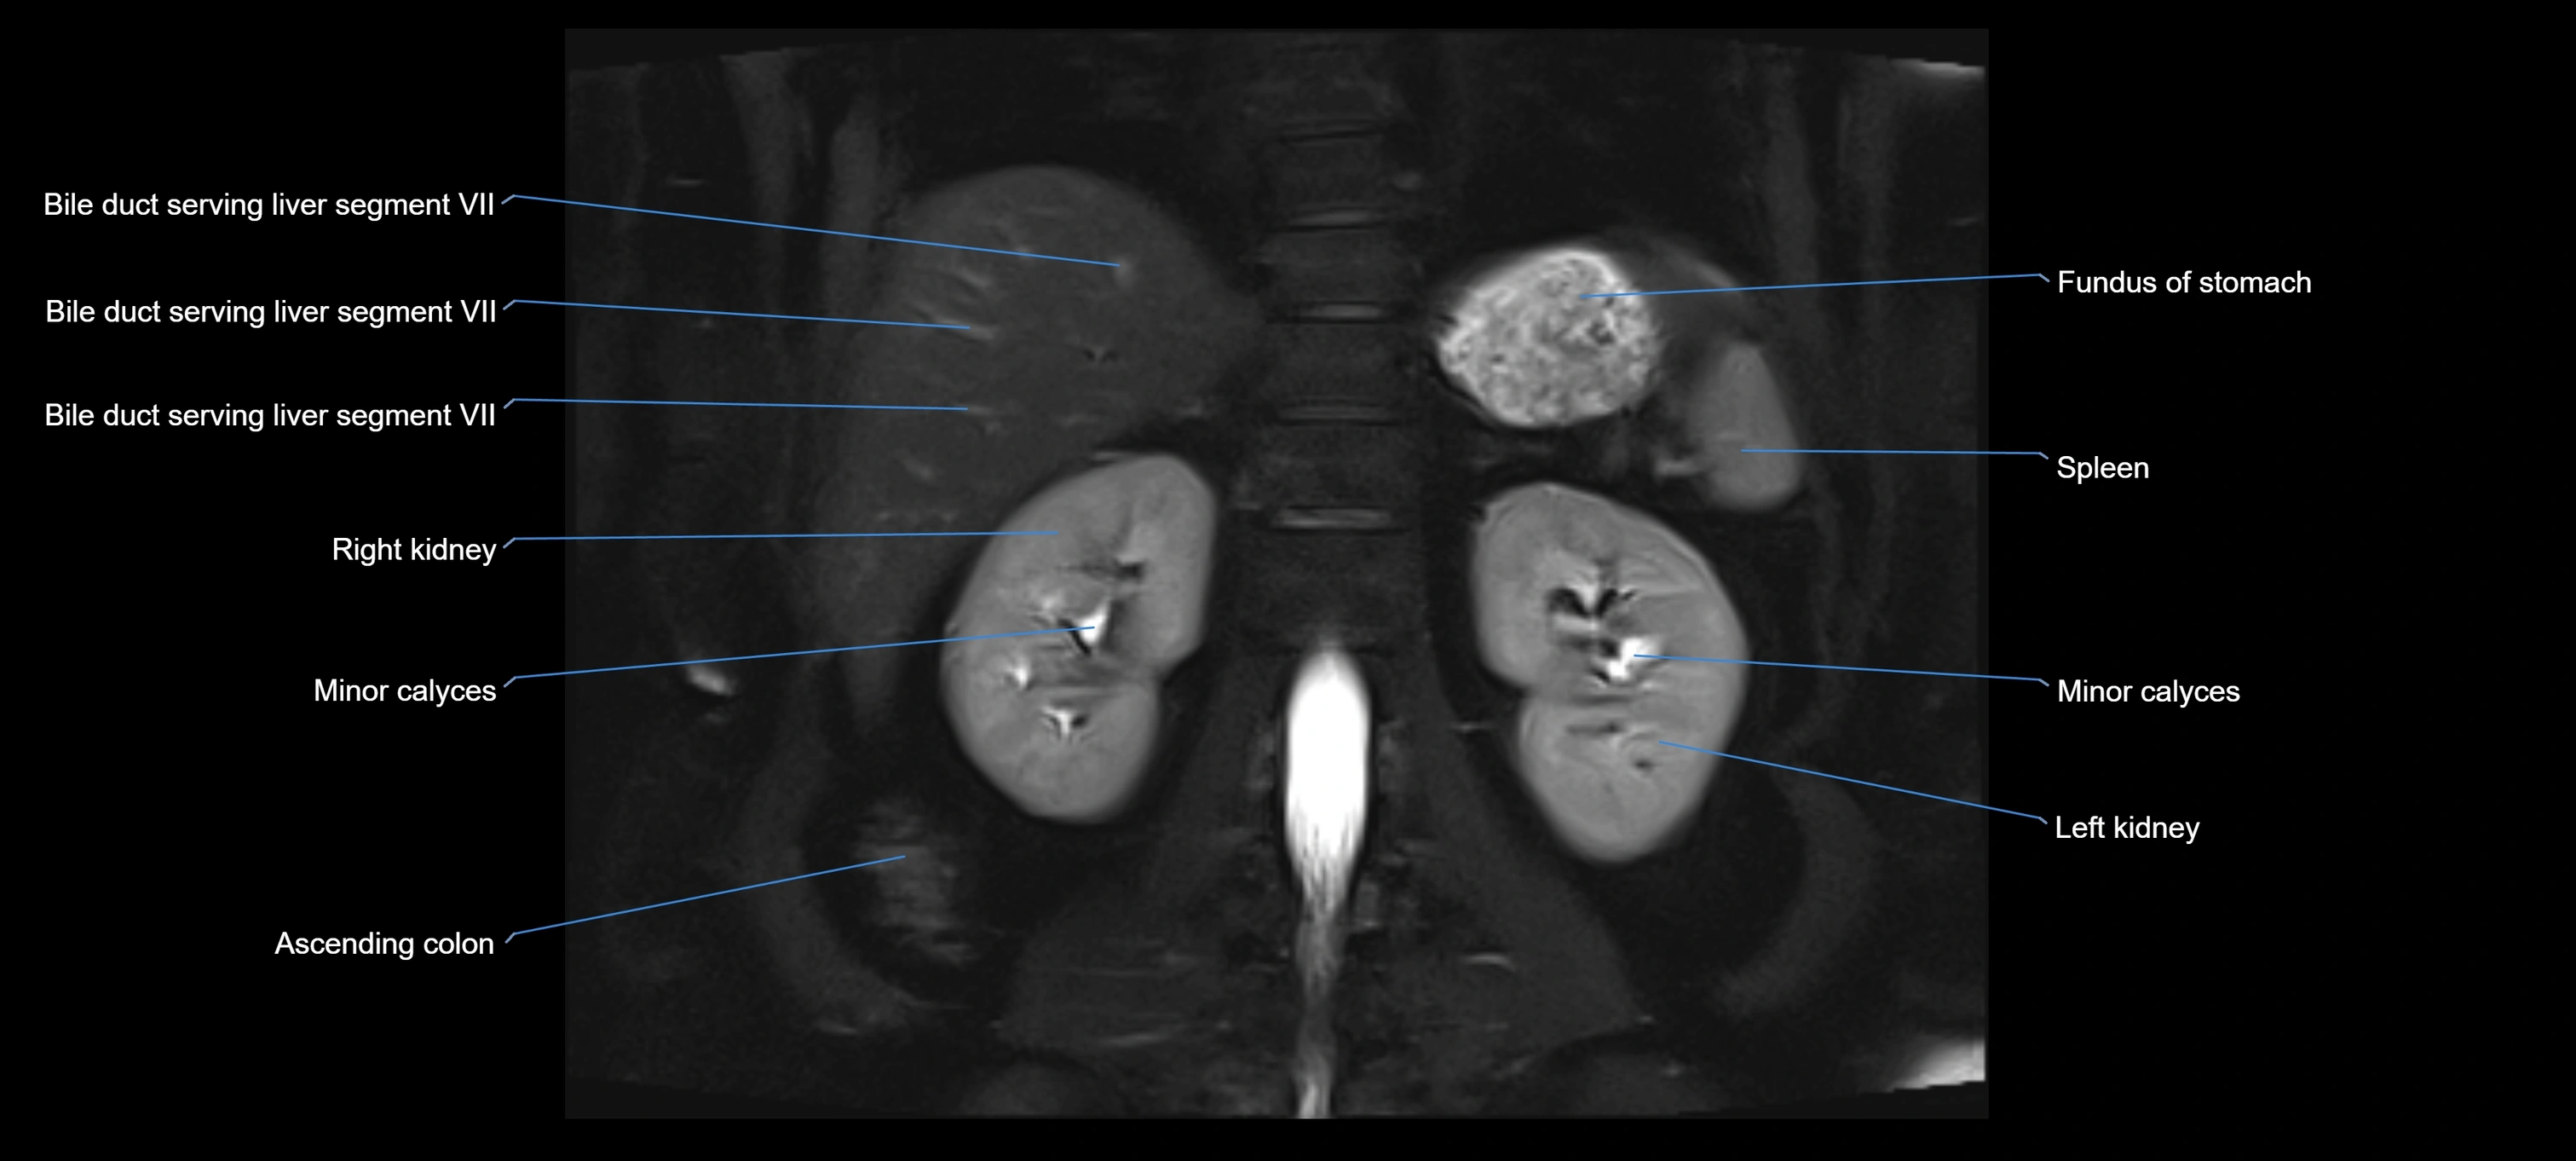

MRI image

image